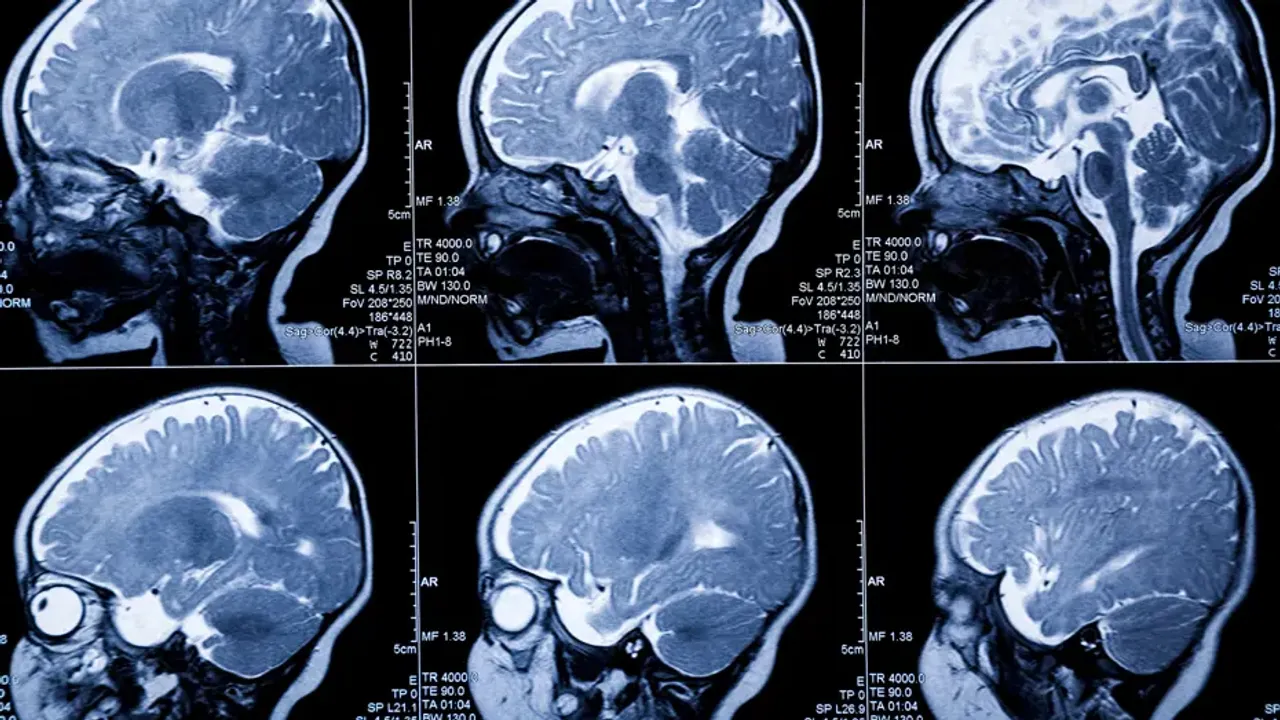

İngiltere’de Cambridge Üniversitesi’ndeki bilim insanları, doğum sırasında oluşabilecek beyin hasarını erken dönemde tespit edebilen yeni bir başlık sistemi geliştirdi. Ultrason ve optik tomografi teknolojilerini bir arada kullanan başlıkla yenidoğanların beyinlerindeki oksijen seviyesinin yüksek hassasiyetle izlenebildiği bildirildi.

İngiltere’de yürütülen araştırmada, yenidoğanların beyinlerinde oksijen seviyesini yüksek hassasiyetle izleyebilen yeni bir görüntüleme teknolojisi tanıtıldı. Yüzücü bonesini andıran ve “Theo” adlı üç haftalık bebek üzerinde test edilen başlık, ultrason ve optik tomografi sistemlerini bir arada kullanıyor.

“FUSION” adı verilen teknolojinin, doğum sırasında beynin yeterli oksijen alamaması sonucu oluşan hipoksiye bağlı hasarların erken dönemde belirlenmesine katkı sunması hedefleniyor. Uzmanlar, mevcut izleme yöntemlerinin uzun vadeli etkileri öngörmekte yetersiz kaldığını, yeni sistemin erken teşhisle tedavinin daha hızlı başlatılmasına imkân sağlayabileceğini belirtiyor.